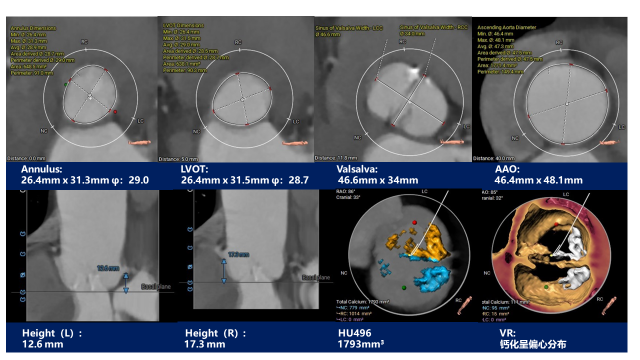

主动脉根部测量

CT特点:Type 0型二叶式主动脉瓣,左右冠不同窦,瓣叶中重度钙化伴增生肥厚,钙化呈偏心性分布;左右冠开口高度可,无冗长瓣叶;近横位心,心室壁肥厚。

瓣上测量

瓣上测量:瓣叶中重度钙化伴增生肥厚,钙化呈偏心性分布,主要分布于瓣叶边缘及前壁交界附着缘。